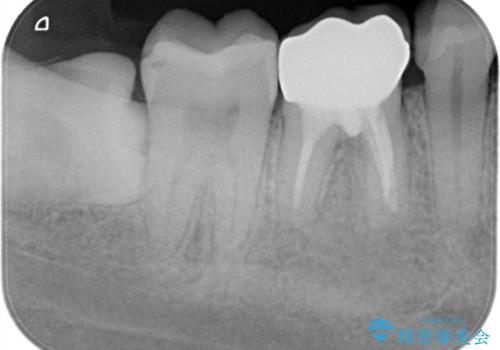

根管治療時に穿孔部位を認め、MTAにて修復し、分岐部の歯周ポケットおよび骨欠損に対しては、再生治療を行うことで、正常な歯周状態の獲得ができました。

歯冠修復はオールセラミッククラウンで行なっております。